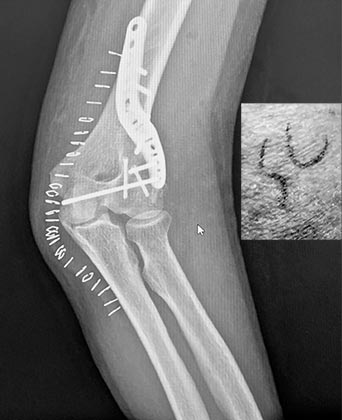

The Titanium Club

Roscoe is my latest friend to join the Titanium Club; he went through his initiation this afternoon. I’m not talking about titanium cameras or bikes; everyone in the Titanium Club has parts of their aging carcasses held together by titanium plates, screws, and other bits of hardware.

Samuel Chun was the master of ceremonies and surgeon for the auspicious occasion, and I can see from one glance at the X-ray, even as a layperson, that he did a great job. Doctor Chung doesn’t suffer from false modesty, and he signed Roscoe’s skin after the long, complex operation.

I think that’s great! Good artists only sign good work, and I’m glad the physician takes pride in his accomplishments. If you’re thinking of joining the Titanium Club, pick up the blower and give him a call.